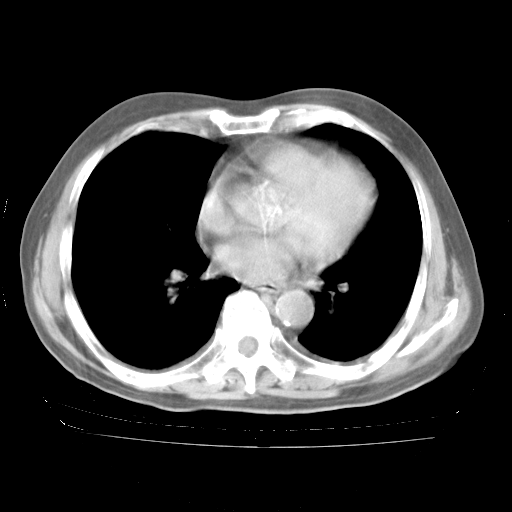

4月28日肺部CT——再次出现类似去年5月9日——透光度降低,“间质性”改变。

1、108#的是4月14日的胸部CT(发此贴时还没看着28日的CT)。14日的胸部CT其实已经出现改变(如108#所述),个人认为28日的胸部CT除纵膈窗疑似有双侧胸膜增厚或少量胸积液(可行胸部B超明确)外,与4月14日对照病变有所加重;2、已经给予“异烟肼、利福平、乙胺丁醇”抗痨治疗?如果是,甲强龙80mg可缓慢减量;如果环磷酰胺已停用,暂不使用;3、中性粒细胞92%,明显升高,目前体温情况?注意合并细菌感染可能,使用左氧氟沙星情况下,是否联用B-内酰胺类抗菌药物?另外是查免疫全套非风湿全套。

今请临免主任会诊后认为:4月14日胸部CT已有双下肺间质性改变。患者病情复发多系激素减量过快不正规所致。目前甲强龙80mg/日,一周后酌情开始减量,不易过快。环磷酰胺若已停用,暂不使用。他同意目前抗菌药物使用,但应考虑是否加用B-内酰胺类抗菌药物(中性细胞明显增高);2、结核复发目前依据不足;3、若免疫全套各项指标正常,考虑多系特发性肺间质炎可能大。4、加强支持,并注意保护胃黏膜。